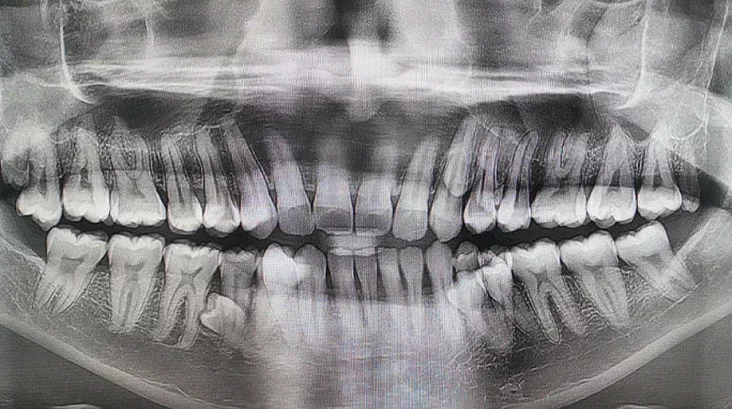

33‑летний житель Малайзии Пратап Муниянди установил необычный мировой рекорд: у него во рту 42 зуба, что на десять больше, чем у среднего человека, который обычно имеет 32. Этот факт был подтвержден и занесен в Книгу рекордов Гиннеса.

Сам мужчина долгое время не подозревал о своей особенности. Об этом стало известно в 2021 году во время семейного разговора, когда он пошутил, что у него может быть больше зубов. Родные насчитали 38, а после рентгеновского исследования выяснилось, что еще четыре зуба не прорезались. В начале 2023 года стоматологи официально подтвердили, что у него всего 42 зуба. При этом большинство из них растут ровно и не вызывают проблем.